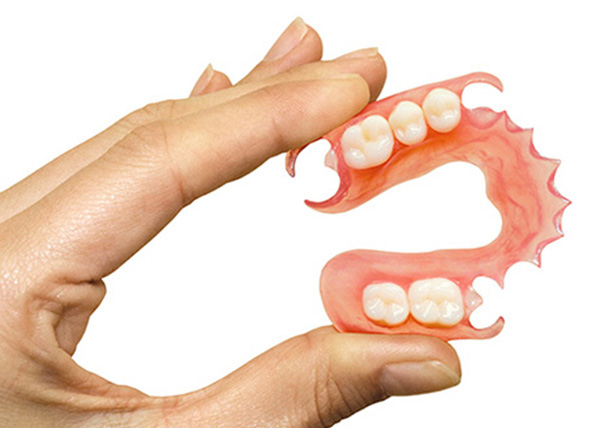

Partial dentures

There are different types of dentures: total and partial. If the patient only has a few teeth partial dentures that fit between the existing teeth are used. Total dentures are used in the case where there are only few or no tooth. The remaining teeth are extracted and a denture mould is taken.